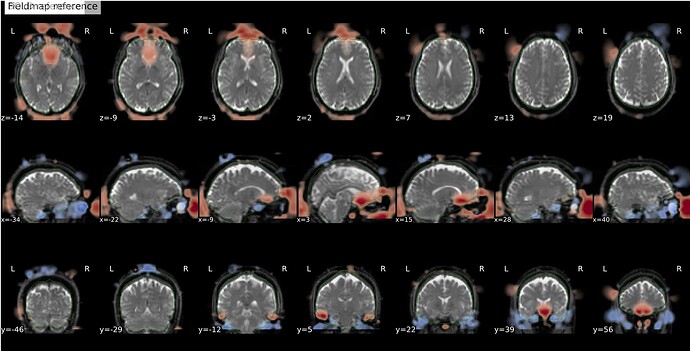

I’m seeing an apparent misalignment in the fmapCoreg reportlet for a PEPOLAR (SE-EPI AP/PA) distortion-correction workflow

- The SDC before/after panel looks okay-ish, suggesting distortion correction itself is likely working somehow, but poor than for subjects where fmap-bold coreg works as expected.

Another example: